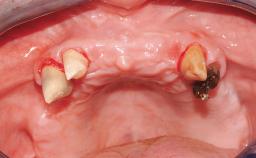

Immediate Loading of Six Implants in the Maxilla and Final Restoration with a Full-Arch CAD/CAM Zirconia FDP

A 63-year-old male patient was referred for a consultation and treatment of partial edentulism in the maxilla. The patient presented with residual anterior teeth and declined a partial removable prosthesis. He reported that the maxillary posterior teeth had been extracted due to mobility and periodontal disease two months before the consultation. The patient’s chief complaint was that his residual maxillary teeth were mobile and that he was unable to chew. The patient’s desire was a stable and comfortable fixed maxillary rehabilitation. The patient was a light smoker (fewer than 10 cigarettes/ day), and his medical history was without significant findings. He was not on any regular medication at the time of consultation. The extraoral examination revealed a normal physiognomy with a correct distribution of the facial thirds. The patient presented a low lip line, and the transition line between teeth and soft tissues was not exposed during a forced smile.

Soft Tissue Anatomy Intact Defective

Bone Volume Horizontally and vertically sufficient Horizontally deficient Deficient vertically or deficient vertically AND horizontally

Soft Tissue Contour and Volume Slightly compromised